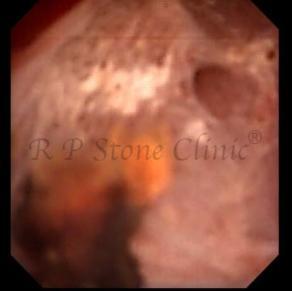

The Below Images Show Small Stones attached to the Renal Papillae.